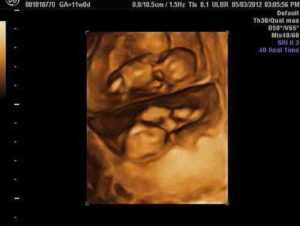

Беременности двойней по неделям не очень сильно разнится в зависимости от типа двойни. Однако определить, кто же родится — близнецы или двойняшки — сможет только исследование УЗИ. На каждом этапе беременности женщина должна подходить к своему здоровью и здоровью будущих малышей ответственно, своевременно посещать врача-гинеколога, и получать у него консультации.

Начиная с 5 недели УЗИ точно показывает, что будет двойня. Следует отметить, что на поздних сроках на УЗИ скорее всего уже не будет видно двойни, т.к. луч УЗИ видит только одного ребенка, расположенного ближе.

На восьмой неделе определить, что будущая мама ждет двух малышей, возможно только с помощью УЗИ матки.

К этому моменту будущие детки достигают длины примерно в 6 см, и будущая мама уже может увидеть их на УЗИ.